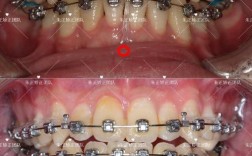

- 正畸治疗: 这是最常见的含义,指通过戴矫治器(牙套、隐形牙套等)来移动牙齿,排列整齐,改善咬合关系和面部美观。绝大多数需要“正畸”的人指的是进行这种牙齿矫正治疗。

- 拥挤: 牙齿太多,空间不足,导致牙齿重叠、扭转、错位,这是最常见的正畸原因之一。

- 深覆合: 上前牙盖过下前牙过多,甚至咬到下牙龈。

- 深覆盖(龅牙): 上前牙过于前突,超出下前牙过多。

- 反颌(地包天): 下前牙咬在上前牙的外面(反合),可能发生在前牙或后牙,影响咀嚼和面型。

- 开颌: 上下前牙或后牙在咬合时无法接触,留有缝隙。

- 锁颌: 上后牙咬在下后牙的颊侧,或下后牙咬在上后牙的颊侧,影响咀嚼和清洁。

(图片来源网络,侵删)- 希望改善因牙齿问题导致的面部轮廓不协调(如嘴凸、瘪嘴、下巴后缩或前突、面部不对称等)。